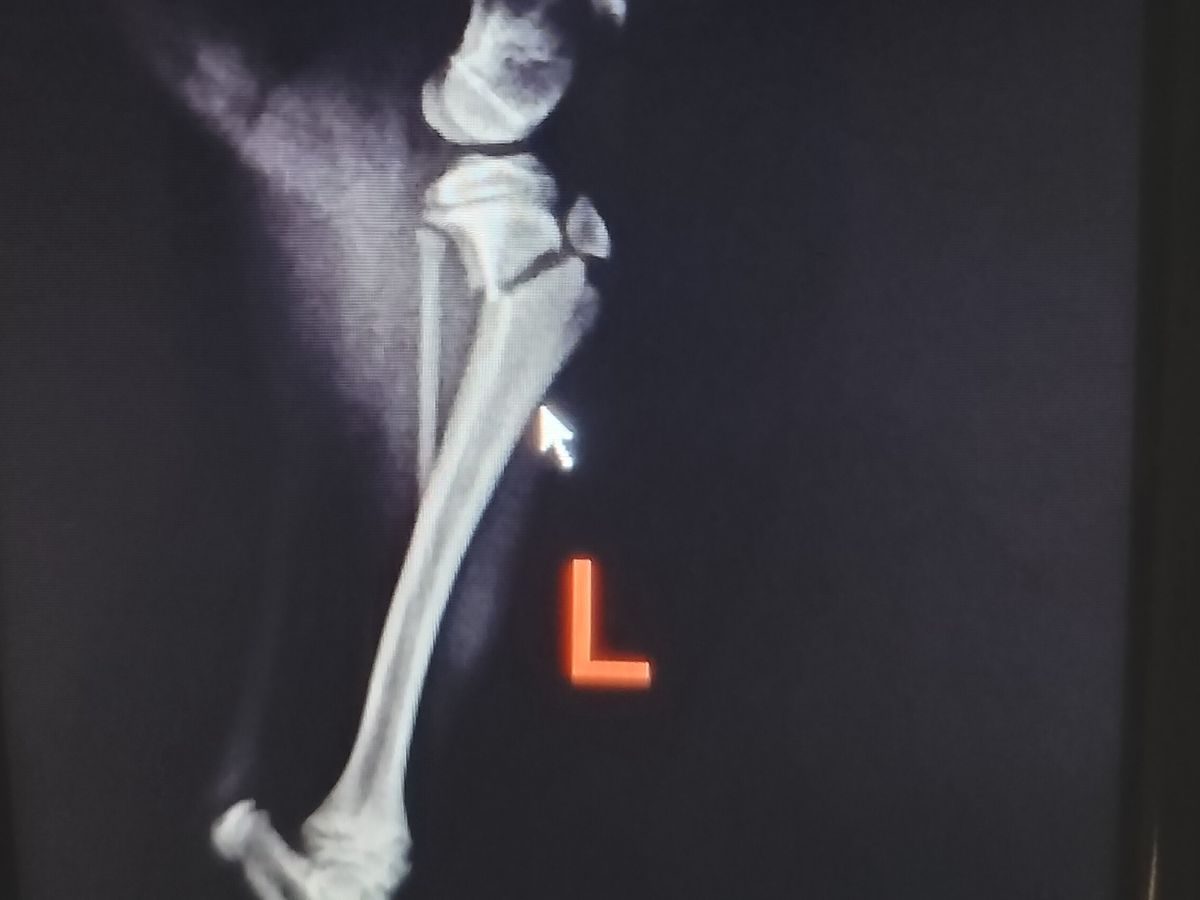

scouting the area three minutes away. Once there they immobilized his leg to avoid further damage and as you can see he has a big fracture and the only explanation might be that he fell from the stairs because he was left out. I am angry, frustrated, in disbelief because I trusted and I shouldn't. I feel like a failed in protecting my furbaby.

The vets office I went to isn't equipped with much and they did what they could and told me to take him to orthopedic surgeon which I did today February 8, 2024. The estimate is included.

I have pain medicine until Saturday I am certain they can prescribe more should I need more time. I am having faith and hope that I receive help during this difficult time to help my furbaby. He is comfortable and isn't in pain but he needs the surgery soon to avoid further damage. I am taking time to be with him around the clock and ensure he doesn't put pressure on his injured leg.